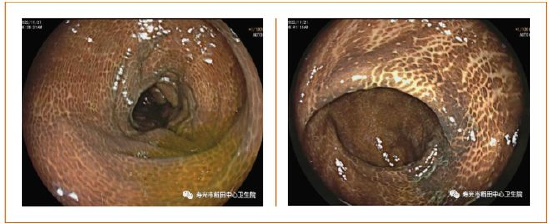

另外,在检查中还发现一些便秘患者,因为长期口服泻药,导致出现结肠黑变病,再次提醒各位长期应用泻药排便的患者,一定要合理用药,保护好肠道微生物生态。典型图片如下。